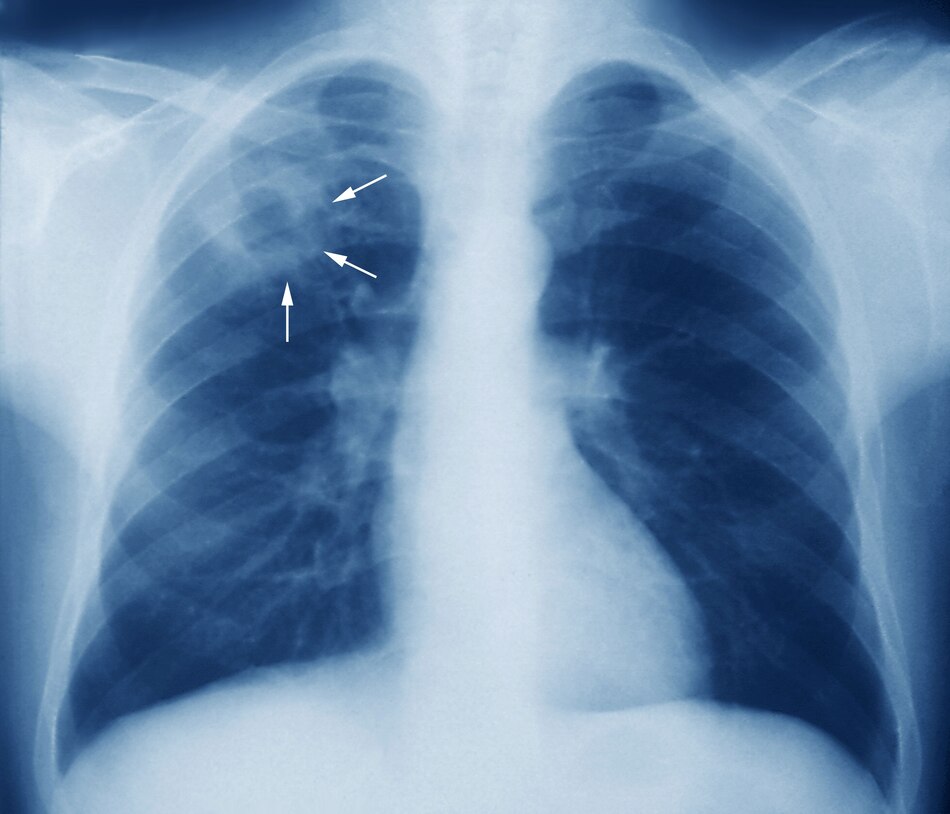

Pero la realidad –añadió– es que todavía se hacen muchos diagnósticos en el hospital cuando el paciente llega con complicaciones. “Un paciente que ya tiene sudoración nocturna, pérdida de peso, fiebre vespertina, posteriormente tos con sangre, en ese momento ya hay una lesión en los pulmones y ese paciente está expectorando muchos bacilos que pueden ser inhalados por cualquier otra persona sana”, subrayó.

Gartner insistió en que si se diagnostica la enfermedad en sus fases iniciales, se evitarán lesiones graves en los pulmones que luego son “irreversibles”. En ese sentido, recalcó que la tuberculosis es tratable, curable y prevenible.